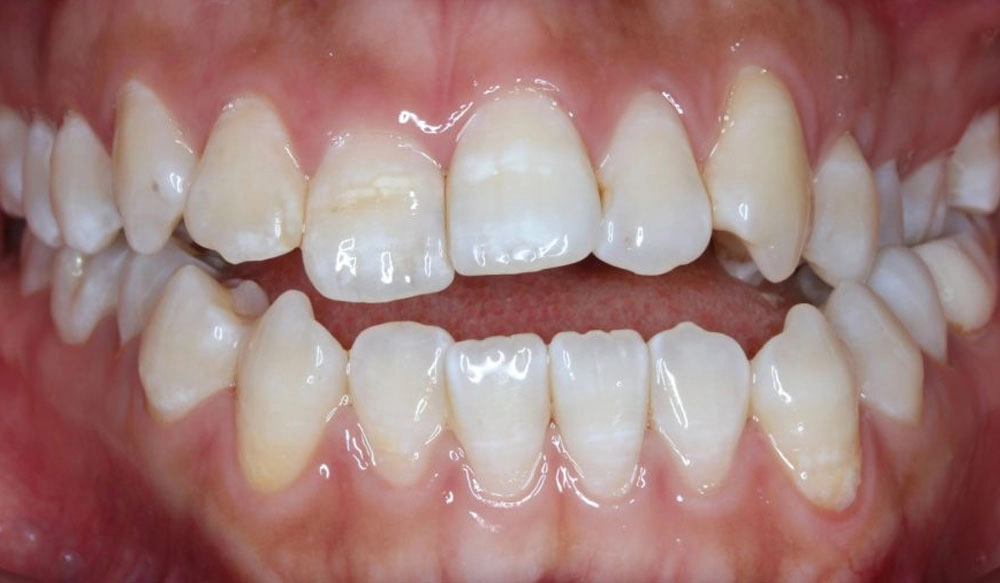

Crowding

Crowding is the condition in which there is a discrepancy between tooth size and space available for the teeth to be aligned in the dental arch

Patient Information:

Age: 17

Gender: female

Invisalign Treatment Option: Invisalign Comprehensive

Total Treatment Time:

29 months